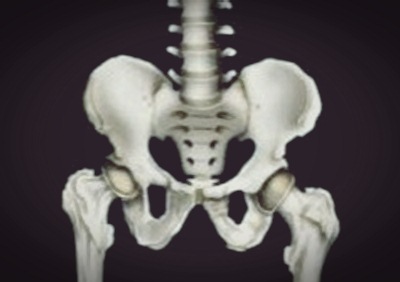

고관절, 구조는

고관절은 우리몸의 187개 관절 중 하나로, 사람에서 가장 큰 관절 중 하나이다. 체중의 1.5에서 최대 10배의 하중을 지탱해주는 역할을 하며 척추와 함께 우리 몸의 기둥 역할을 한다.

고관절의 구조를 보면 재미있는 부분이 있다. 대퇴골두라 불리는 공처럼 둥근 넓적다리뼈의 머리 부분과 이 부분을 감싸는 절구 모양으로 생긴 골반골인 비연구골로 구성되어 있다. 주로 앞뒤로 움직이는 무릎관절과 다르게 고관절의 움직임은 앞뒤, 좌우, 회전 등 움직임의 범위가 넓은 것이 특징이다.

이처럼 골반과 다리를 연결해주며, 체중 지탱과 함께 보행을 돕는 핵심적인 역할을 하기 때문에 그 구조가 안정적이다. 이런 안정적인 구조에도 불구하고 고관절 건강을 챙기지 않으면 고관절 충돌 증후군 등 관절 질환을 호소할 수 있다.